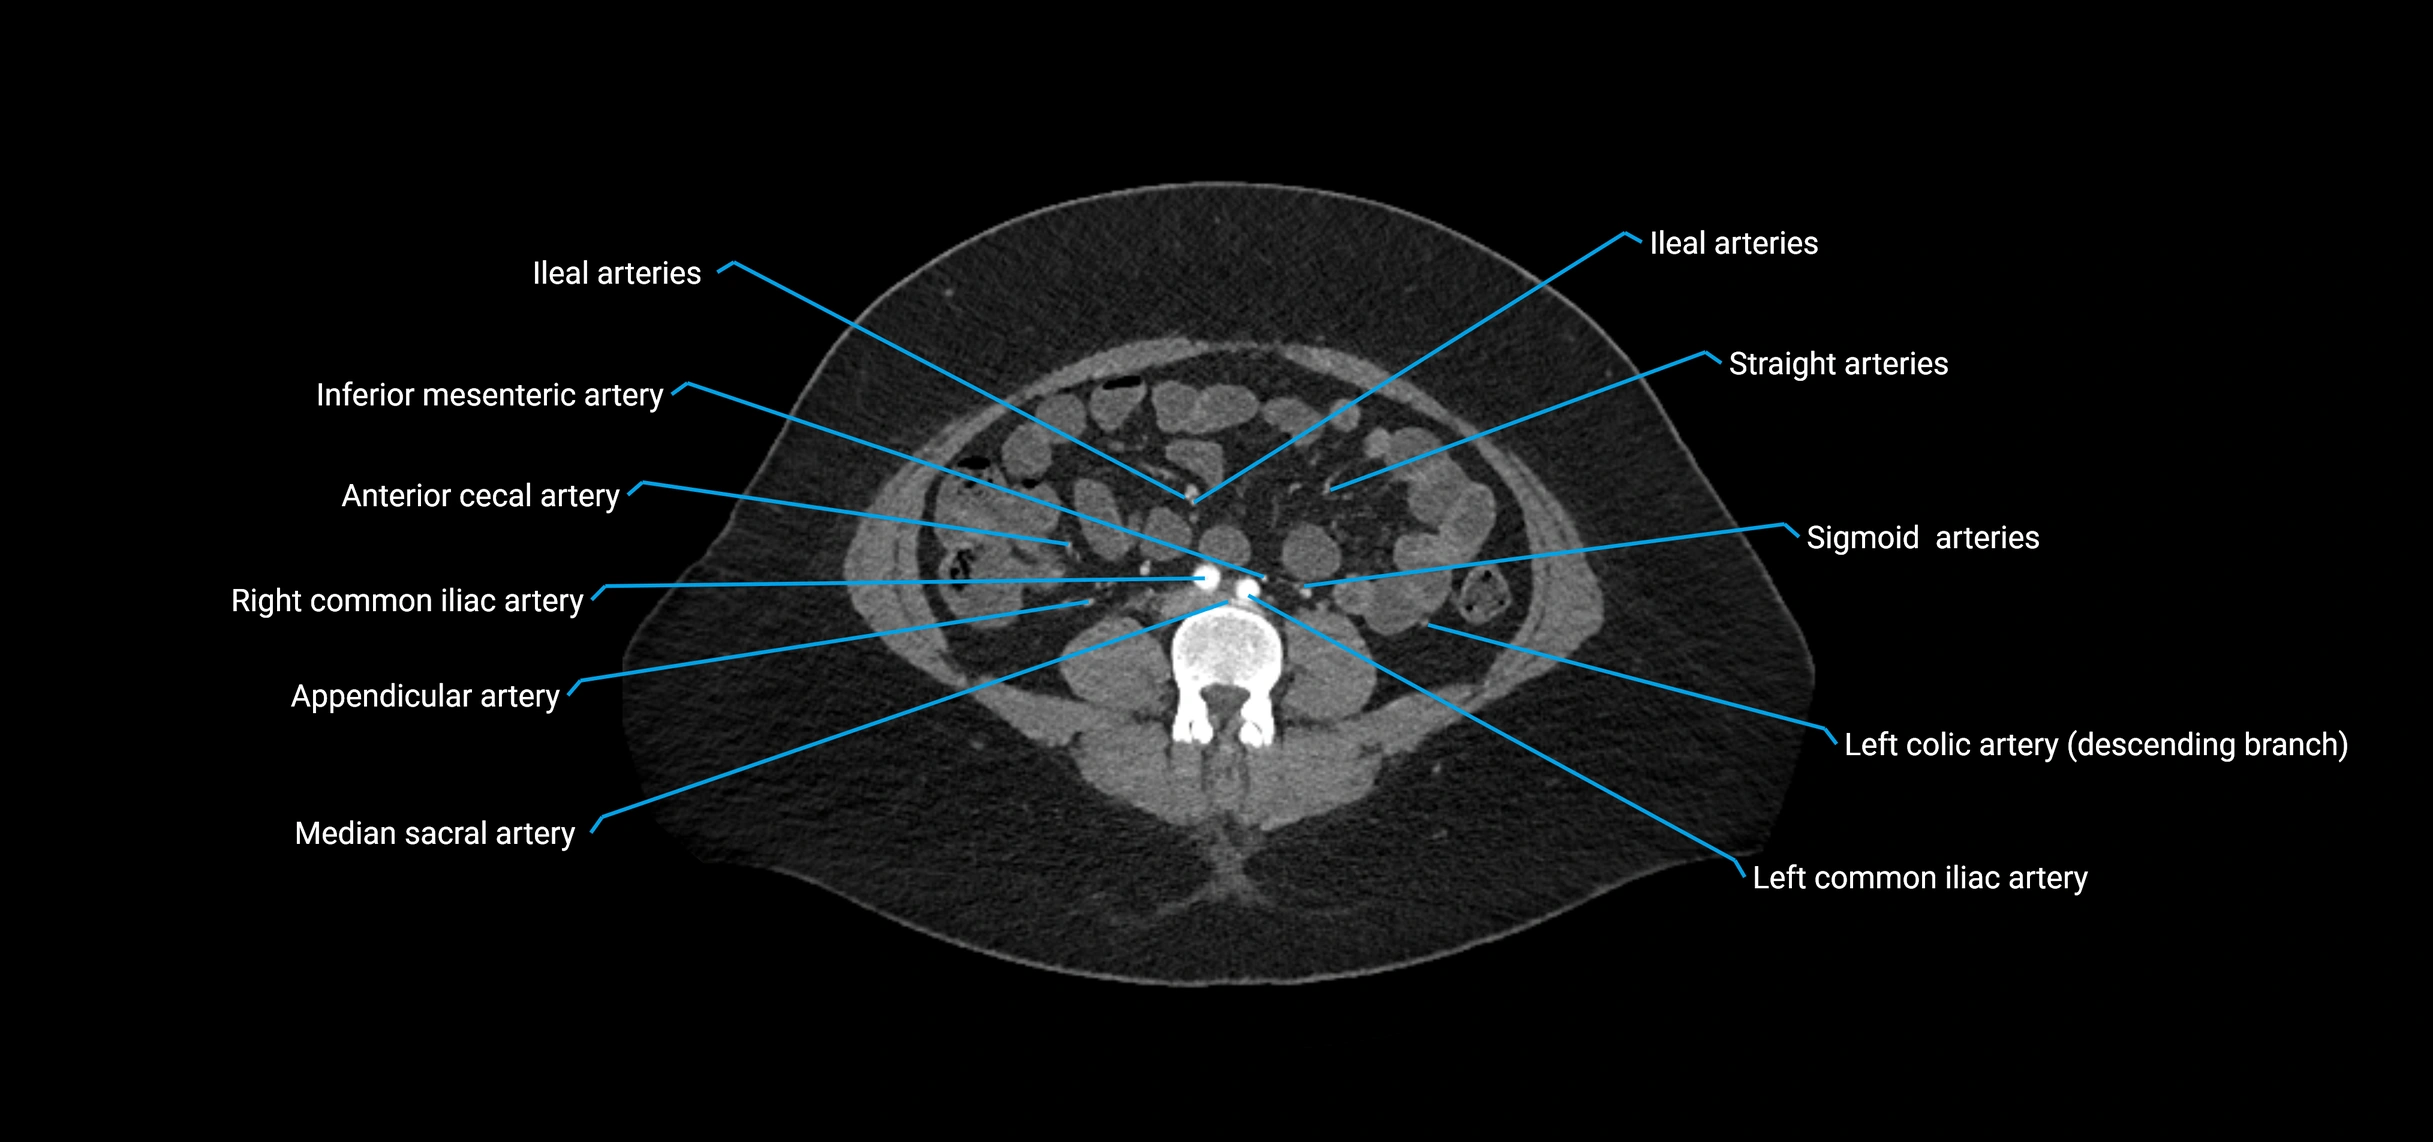

Contrast-enhanced CT (CTA):

• Gold standard for abdominal aortic imaging

• Provides excellent detail of lumen, wall, aneurysm, thrombus, and branch vessels

• Multiplanar and 3D reconstructions help in aneurysm measurement, stent graft planning, and dissection evaluation

• Detects acute rupture, traumatic injury, or occlusion with high sensitivity